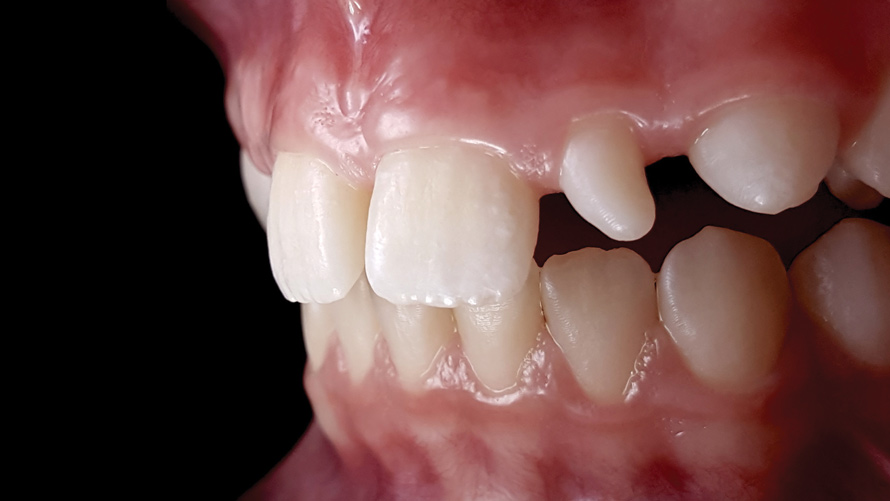

One of the main advantages that smartphone cameras have over DSLR cameras is that nearly everyone is already very familiar with the technology; therefore, the incorporation of these devices into everyday practice does not require learning a new and unfamiliar skill set. The task of producing a series of high-quality clinical photographs for routine examinations (Figure 8), esthetic treatment planning (Figure 9 through Figure 11), or specialty care (Figure 12 and Figure 13) can be delegated with confidence to any staff member during the patient's initial office visit and will generally require less than 5 minutes of time to complete. When a DSLR camera is used, evaluation of the intraoral images either takes place on the small viewfinder built into the camera or necessitates the physical removal of the memory card from the camera to downloaded the images onto a computer for review. An added bonus of smartphone dental photography is that the phone's screen now replaces the much smaller viewfinder of a DSLR camera and provides the clinician with the ability to view and zoom into the patient images on a 5- to 6-inch, high-definition display.

(9.) Preoperative esthetic case documentation using a smartphone and an EALS device.

Figure 9

(10.) Preoperative esthetic case documentation using a smartphone and an EALS device.

Figure 10

(11.) Preoperative esthetic case documentation using a smartphone and an EALS device.

Figure 11

(12.) Intraoral photographs taken with a smartphone and an EALS device for orthodontic evaluation.

Figure 12

(13.) Intraoral photographs taken with a smartphone and an EALS device for orthodontic evaluation.

Figure 13